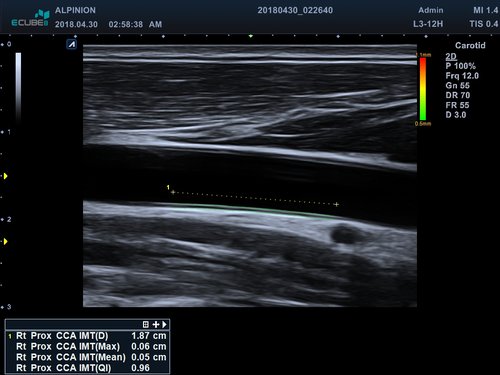

• L3-12T (3-12 MHz) für Ultraschalluntersuchungen in Bereichen Brust, Notfallmedizin, MSK, Vaskulär, Kleine Organe, Appendix

• M-Modus, Auto IMT, CV Measurement and Report, EKG, Cube Strain, Stressecho, Tissue Doppler Imaging (Kardiologie)